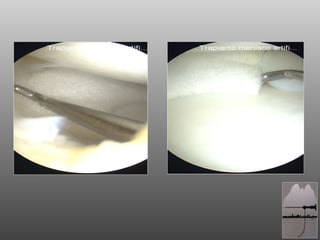

Indicazioni Lacerazione mediale o laterale non riparabile del menisco, con necessità di meniscectomia parziale Integrità delle inserzioni anteriore e posteriore del menisco  Bordo integro sull'intera circonferenza del menisco LCA integro Arto inferiore in asse Danno condrale max 2° Pazienti in grado di comprendere e seguire un programma di riabilitazione post-operatoria

Indicazioni Lacerazione medialeo laterale non riparabile del menisco, con necessità di meniscectomia parziale Integrità delle inserzioni anteriore e posteriore del menisco Bordo integro sull'intera circonferenza del menisco LCA integro Arto inferiore in asse Danno condrale max 2° Pazienti in grado di comprendere e seguire un programma di riabilitazione post-operatoria